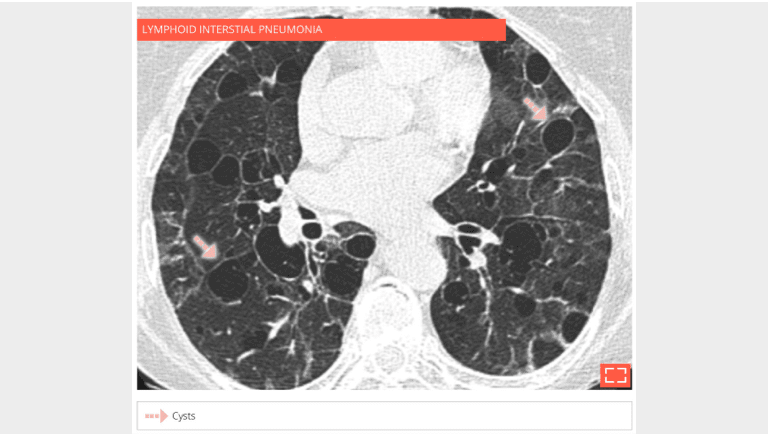

72-year-old woman with Sjögren’s syndrome and lymphoid interstitial pneumonia. HRCT shows bilateral groundglass opacities and multiple thin-walled cysts.